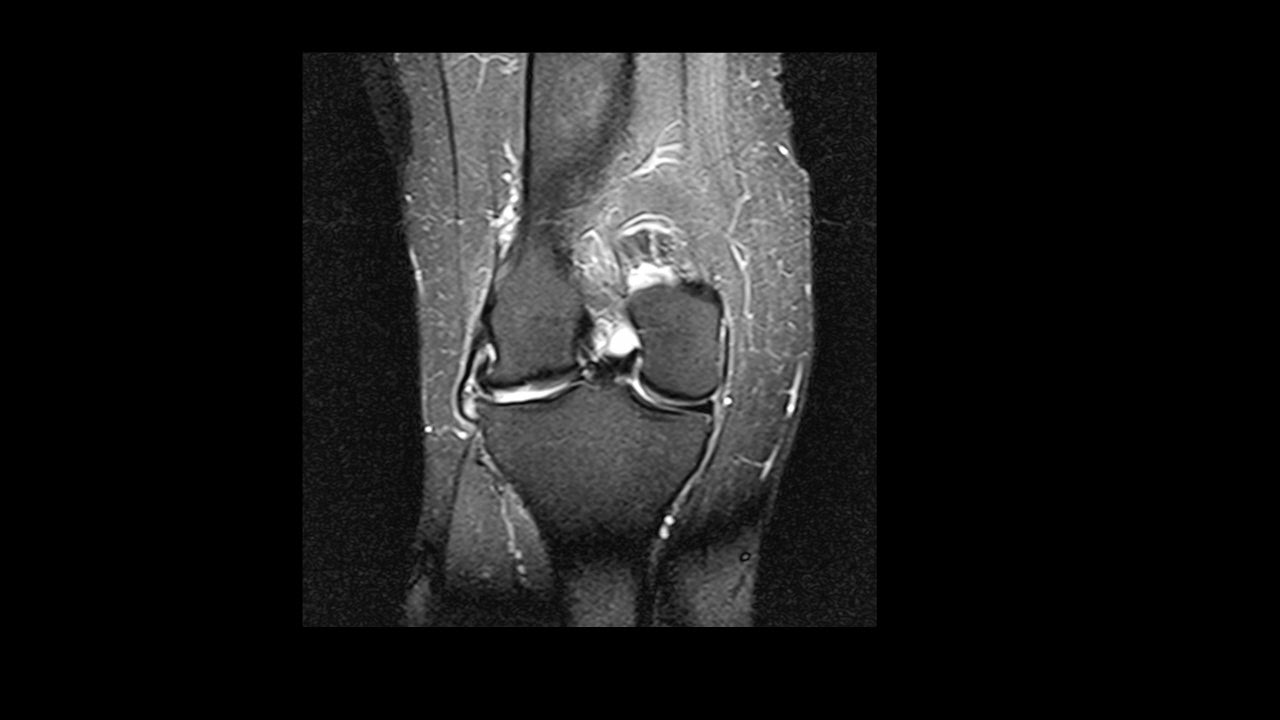

Paciente de 50 años que consulta por importante dolor de rodilla con aumento de partes blandas.

Se le realiza RM observándose las siguientes imágenes:

¿Qué hallazgos observa?

Solución de continuidad y cambios de señal del ligamento cruzado posterior con quiste paramensical

¿El diagnóstico más probable es:?

Rotura compleja en asa de cubo del menisco externo